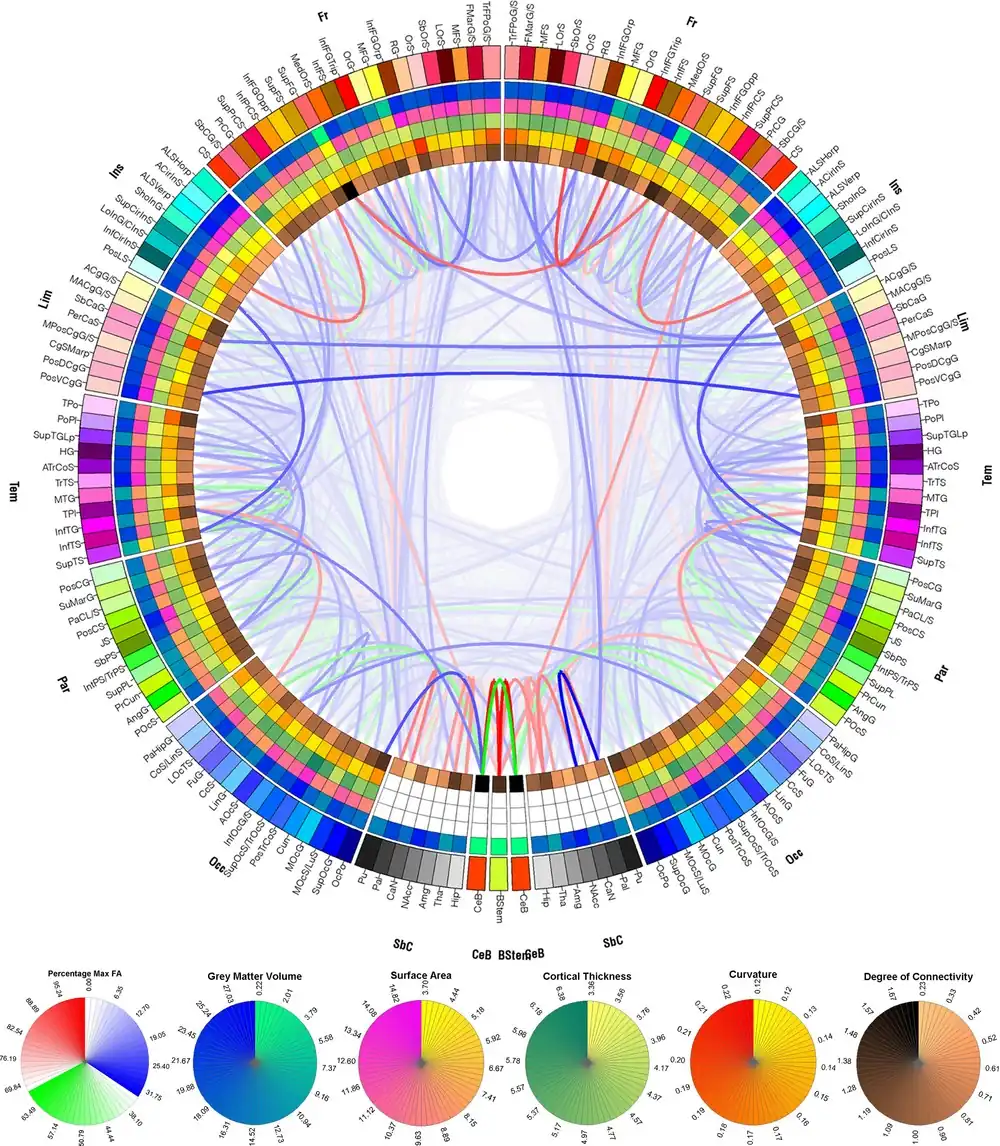

Connectograms are graphical representations of connectomics, the field of study dedicated to mapping and interpreting all of the white matter fiber connections in the human brain. These circular graphs based on diffusion MRI data utilize graph theory to demonstrate the white matter connections and cortical characteristics for single structures, single subjects, or populations.

Connectograms are circular, with the left half depicting the left hemisphere and the right half depicting the right hemisphere. The hemispheres are further broken down into frontal lobe, insular cortex, limbic lobe, temporal lobe, parietal lobe, occipital lobe, subcortical structures, and cerebellum. At the bottom the brain stem is also represented between the two hemispheres. Within these lobes, each cortical area is labeled with an abbreviation and assigned its own color, which can be used to designate these same cortical regions in other figures, such as the parcellated brain surfaces in the adjacent image, so that the reader can find the corresponding cortical areas on a geometrically accurate surface and see exactly how disparate the connected regions may be. Inside the cortical surface ring, the concentric circles each represent different attributes of the corresponding cortical regions. In order from outermost to innermost, these metric rings represent the grey matter volume, surface area, cortical thickness, curvature, and degree of connectivity (the relative proportion of fibers initiating or terminating in the region compared to the whole brain). Inside these circles, lines connect regions that are found to be structurally connected. The relative density (number of fibers) of these connections is reflected in the opacity of the lines, so that one can easily compare various connections and their structural importance. The fractional anisotropy of each connection is reflected in its color.[1]

With the recent concerted push to map all of the human brain and its connections,[8][9] it has become increasingly important to find ways to graphically represent the large amounts of data involved in connectomics. Most other representations of the connectome use 3 dimensions, and therefore require an interactive graphical user interface.[1] The connectogram can display 83 cortical regions within each hemisphere, and visually display which areas are structurally connected, all on a flat surface. It is therefore conveniently filed in patient records, or to display in print. The graphs were originally developed using the visualization tool called Circos.[10][11]

Connectograms can represent the averages of cortical metrics (grey matter volume, surface area, cortical thickness, curvature, and degree of connectivity), as well as tractography data, such as the average densities and fractional anisotropy of the connections, across populations of any size. This allows for visual and statistical comparison between groups such as males and females,[14] differing age cohorts, or healthy controls and patients. Some versions have been used to analyze how partitioned networks are in patient populations[15] or the relative balance between inter- and intra-hemispheric connections.[16]